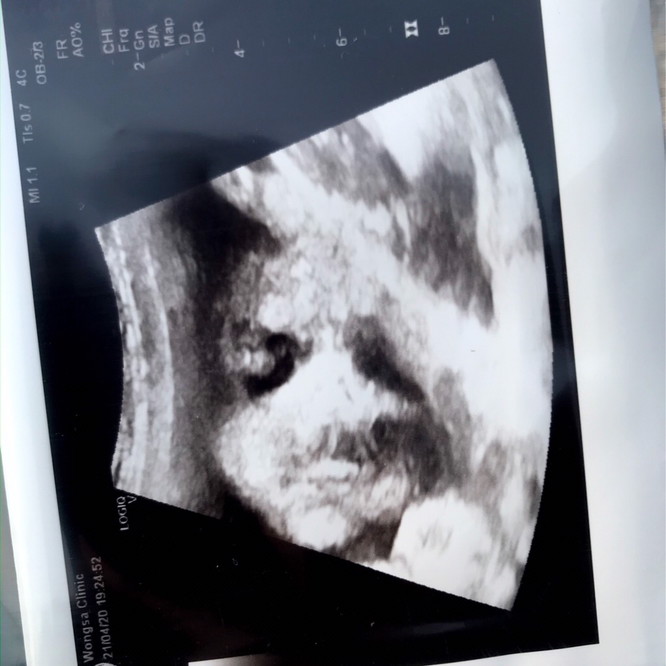

บ้านนี้ 14 ก.ค 63 ค่ะ ☺️